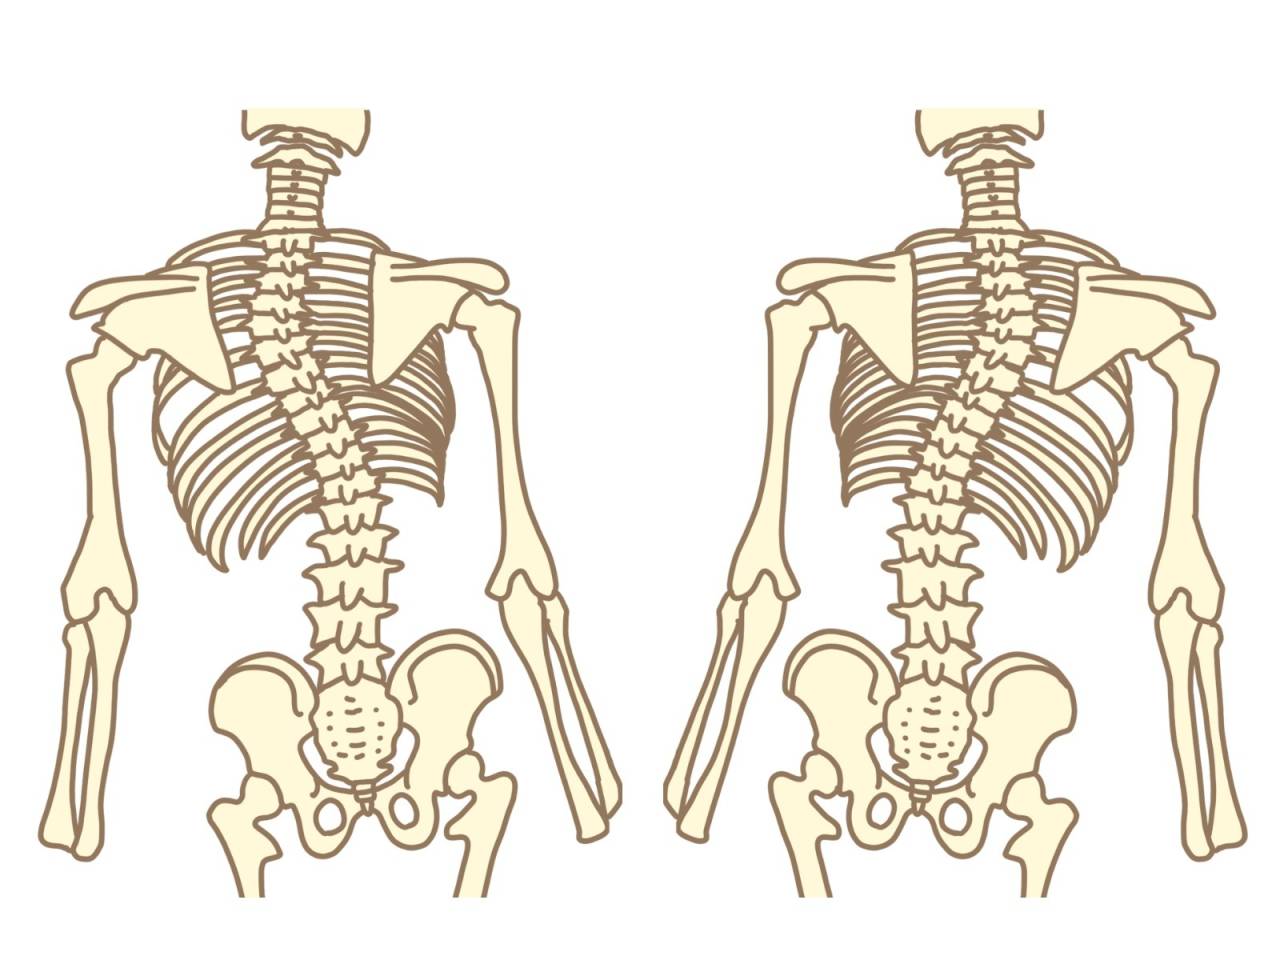

- 背骨

- 歪み

- 骨盤

- 側彎症